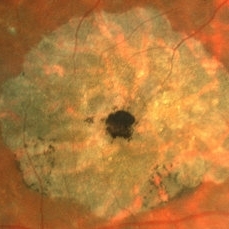

B-FAF in Stargardt's Disease

B-FAF in Stargardt's Disease

Jul 4 2024 by Tejaswita Verma

Blue fundus autofluorescence showing hypoautofluorescence picture of a 28 year old male with 6/60 vision in BE in a case of Stargardt's disease.

Photographer: DR. TEJASWITA VERMA

Imaging device: MIRANTE

Condition/keywords: fundus autofluorescence (FAF), hereditary macular dystrophy, Stargardt disease